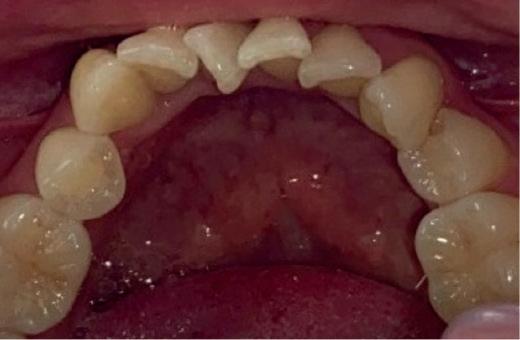

EthOss® is a 100% synthetic bone graft material for dental implant surgery. With no risk of cross-contamination, EthOss® works with the body’s healing process by creating a calciumrich environment and is completely absorbed.